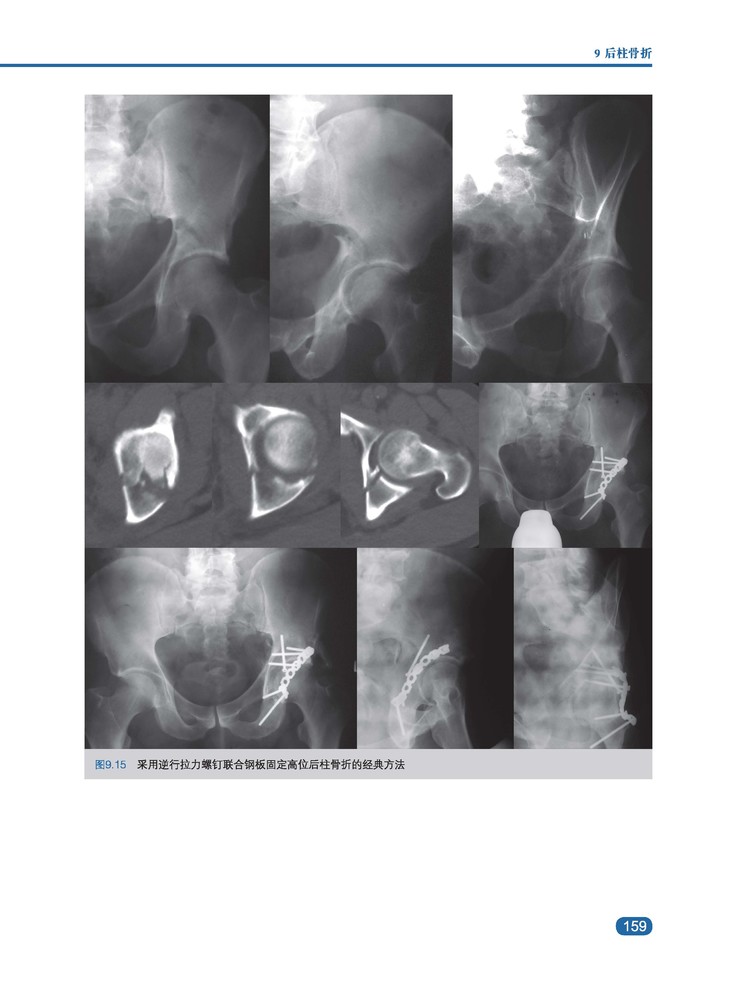

内容简介:髋臼骨折的罕见性和骨折类型的多样性使骨科医生面临巨大挑战。髋关节与周围神经血管结构密切相关,因此,髋关节手术需要特别小心,以保持长期的生物力学稳定性并延缓中青年患者创伤后骨关节炎的发展。本书旨在为骨科医生提供诊断和评估髋臼骨折的策略,适应个体化治疗的需求,采取解剖学引导下的恰当的复位和固定方法。全书图文并茂,基础部分从髋臼外科解剖、生物力学、影像学诊断、髋臼骨折分型、流行病学、治疗适应证及计划、手术入路等方面进行详细讲解。临床部分,按照Letournel分型对各类型髋臼骨折分别从骨折特点、影像学标准、病理生物力学、合并伤、髋关节稳定性、骨折生物力学、适应证、内固定技术、预后等方面结合最新临床数据加以系统分析阐述。此外,结合解剖学及影像学系统介绍了髋臼特殊螺钉的定位及操作技巧。最后,本书详细介绍了老年及儿童髋臼骨折的特点、分型、治疗、预后,以及异位骨化及血栓栓塞等并发症的发生、预防及预后问题。

· 400余幅高质量全彩示意图、影像图、术中图片,全方位展示髋臼骨折的诊断、适应证与治疗策略。